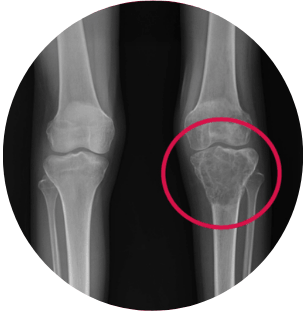

A 26 years old patient came to MIOT International with severe pain in the left knee and an inability to walk. What initially appeared as a musculoskeletal issue was soon diagnosed as something far more serious – a large, rare tumour involving the upper part of the leg bone near the knee. The location of the tumour made this a high-risk and limb-threatening condition. Conventional treatment would likely have resulted in permanent loss of knee movement, or even loss of the leg.

Imaging and diagnostic tests revealed a large tumour affecting the upper tibia (leg bone near the knee). The growth was aggressive and located very close to major blood vessels and nerves. This placed the patient at high risk of limb loss and potential malignant transformation.

Before

After